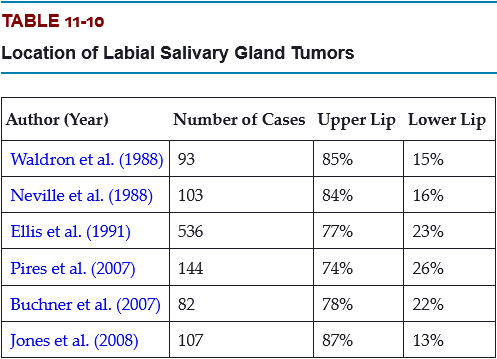

Which is a more common location for minor salivary gland tumors, the upper lip or the lower lip?

Labial tumors are significantly more common in the upper lip, which accounts for 74% to 87% of all lip tumors.